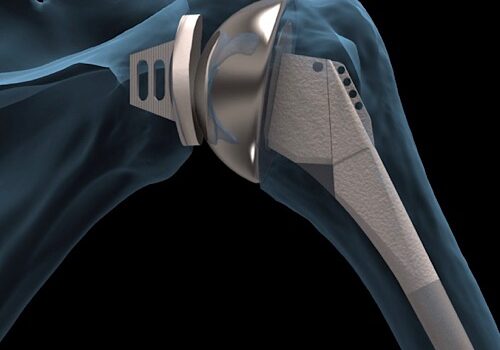

Antes de mais nada, a prótese de ombro oferece uma solução eficaz para pacientes que sofrem com dores intensas e perda de mobilidade devido ao desgaste articular. Dessa forma, o procedimento devolve a funcionalidade da articulação e proporciona mais qualidade de vida a quem enfrenta limitações severas. Quando a prótese […]